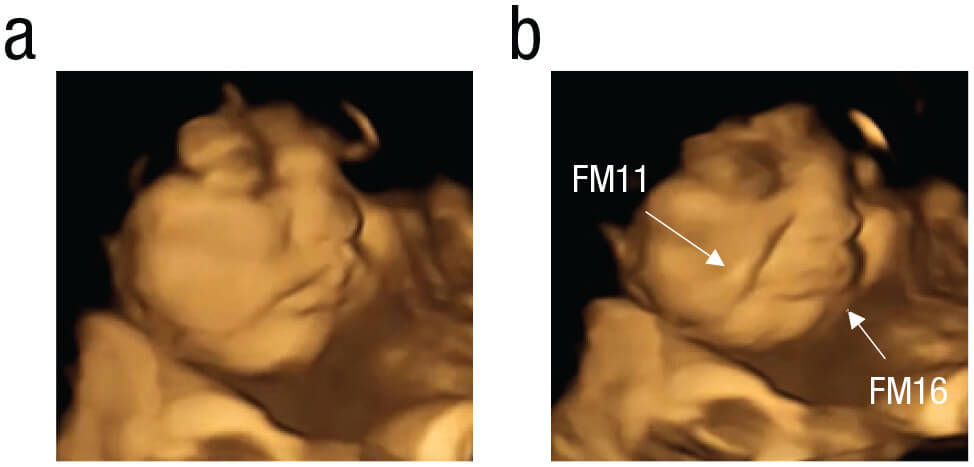

孕婦攝取羽衣甘藍味膠囊後,胎兒傾向露出哭臉。(圖片來源/SAGE Journals)

結果發現,只需要少量的胡蘿蔔或羽衣甘藍粉,就可以刺激胎兒的反應。母親食用羽衣甘藍的膠囊時,胎兒表現出哭泣表情的頻率大約是服用紅蘿蔔膠囊或不服用膠囊時的2倍。母親服用紅蘿蔔膠囊時,胎兒表現出笑臉的頻率大約是母親吞下羽衣甘藍膠囊或不吞下膠囊時的2倍。

也就是說,暴露在胡蘿蔔味道的胎兒,表情更多出現「唇角拉扯」和笑臉;而暴露在苦味較多的羽衣甘藍味道的胎兒,表情較多出現「上下唇翹起」的哭臉。

孕婦攝取胡蘿蔔味膠囊後,胎兒傾向露出笑臉。(圖片來源/SAGE Journals)